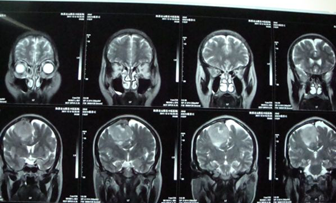

MRI:右顶窦镰旁占位、考虑右顶窦镰旁脑癌(附件如下:)。

诊断:右侧顶窦镰旁脑癌